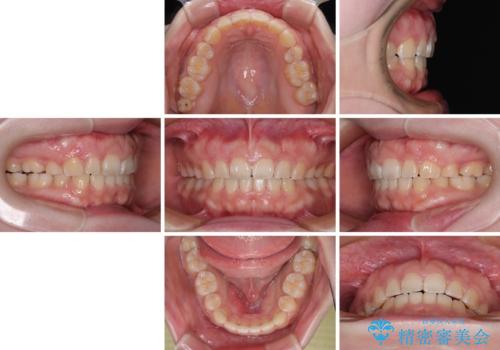

- 出っ歯と口の閉じにくさ、デコボコを気にして来院された患者様です。

口元の突出感を改善するため、上下左右第一小臼歯4本の抜歯を行い、ワイヤー装置による矯正治療を行うこととしました。

抜歯矯正を行ったことで、顎先のつっぱり感や口元の閉じにくさを解消することができました。